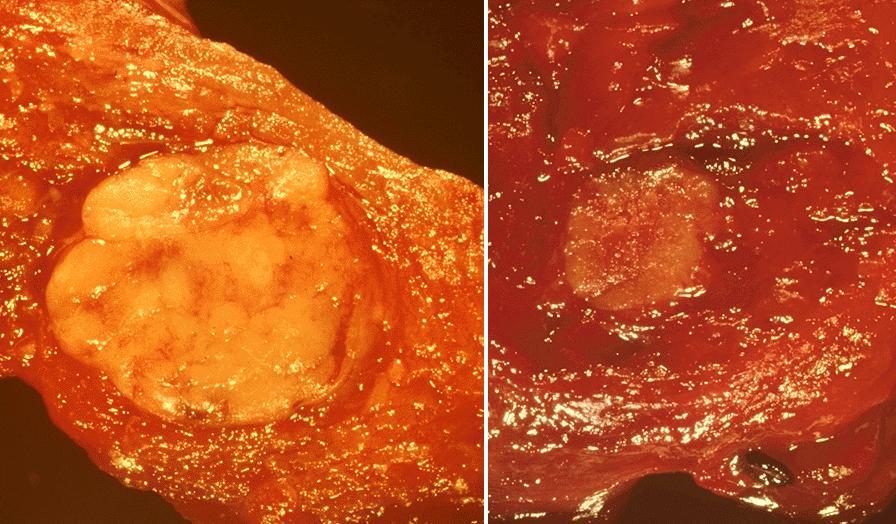

Gross description

- Sporadic: typically presents as a single circumscribed but nonencapsulated, gray-tan mass

- Familial: generally bilateral / multiple foci

- Solid, gray-tan-yellow, firm, may be infiltrative

- Larger lesions have hemorrhage and necrosis, tumor usually in mid or upper portion of gland (with higher density of C cells)

- < 1 cm in size is called microcarcinoma; if < 0.5 cm, associated with a complete absence of clinically detectable metastatic disease (Ann Surg Oncol 2009;16:2875)

Gross images

Contributed by Mark R. Wick, M.D.

AFIP images